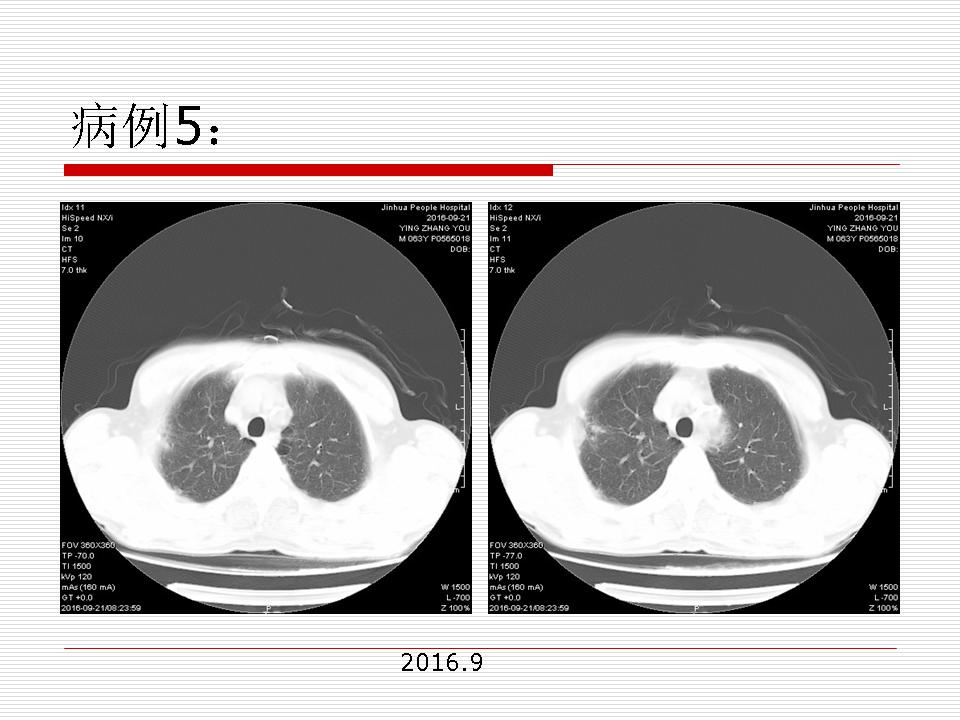

肺部阴影永恒且最重需要鉴别的是:到底是炎症还是肿瘤?但临床的病例中的影像表现难以界定或有些肿瘤特征,同时又有些炎症特点是非常常见的情况。作为临床医生我们怎么去总结分析,并找到之所以是炎症或之所以是肿瘤的细微差别或特点非常重要,也非常有用。2019.12.7浙江省2019年胸心外科学学术年会在宁波召开时,我的临床病例分析与经验总结<那些像肺癌的炎症与像炎症的肺癌>获得在大会交流的机会,以下为该PPT的内容,与你分享,希望对同道有益,有借鉴与启迪。若有探讨与进一不完善的建议,欢迎文末留言讨论: